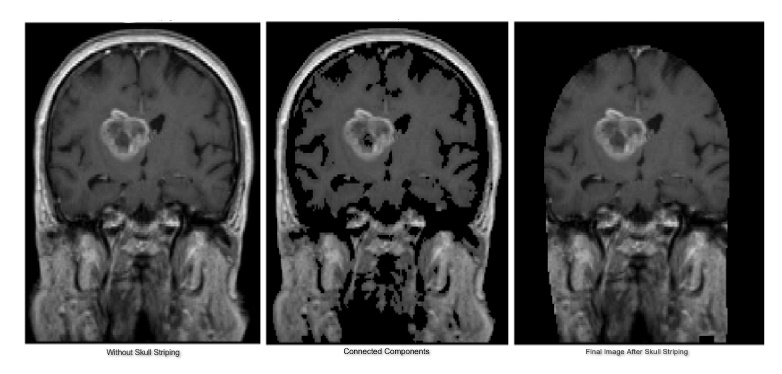

4. Skull Stripping – After removing the bias and the noise skull striping is performed. Skull stripping is an important step to pre-process the image. It is a process of removing the unwanted part in the MRI image like extra tissue, cortical surface, etc. To apply skull stripping we need to first check if the MRI scan is bimodal. This will help us verify if the image can be split into two different intensity classes. If the MRI scan is bimodal, we can proceed to apply Otsu’s method of image thresholding which will give us a binary mask of the brain. Using the threshold, the brain can be extracted by finding the largest connected component. But sometimes when the input image is noisy the extracted brain image might contain many holes in it. Which is why we also need to use a Closing Transformation to close the holes and extract the brain properly. Following 7a shows the input image, 7b shows an attempt to extract the brain without applying closing transformation and 7c shows the final image after applying Closing Transformation. As visible from the final image, Skull Stripping has allowed us to reduce noise considerably.

Refer to caption

Figure 7: Skull Striping